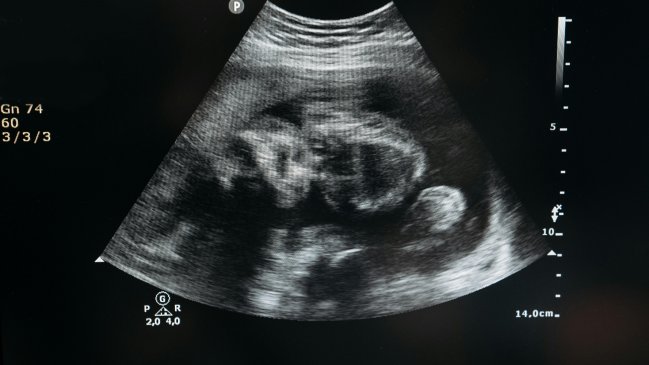

Por último, realizaron una LCC o longitud coronilla-rabadilla, una prueba que mide la distancia entre la cabeza y las nalgas del embrión para determinar el tamaño y desarrollo del feto, y midieron el volumen del saco vitelino a las siete, las nueve y las 11 semanas de gestación.

Observaron que el consumo de UPF en mujeres no estaba relacionado de manera consistente con el riesgo de baja fertilidad ni con el tiempo hasta el embarazo, pero sí con un crecimiento embrionario y un tamaño del saco vitelino ligeramente menores hacia la séptima semana de gestación (lo que se asocia con un mayor riesgo de aborto espontáneo y parto prematuro).

Además, un crecimiento embrionario más lento en el primer trimestre se asocia con problemas en el parto, como parto prematuro (antes de las 37 semanas), bajo peso al nacer, y un mayor riesgo de problemas cardíacos y de los vasos sanguíneos en la infancia, recuerdan los autores.